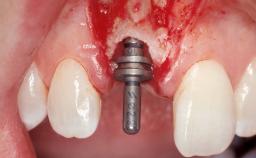

Immediate Flapless Placement of an Implant in a Maxillary Left Central Incisor Site

A 42-year-old female patient was referred to our clinic at the School of Dentistry of the University of São Paulo in November 2004, presenting a deficient restoration in the upper left central incisor. The clinical examination revealed no gingival retraction or any signs of gingival inflammation and, therefore, previous periodontal treatment was not considered. The patient presented a high lip line at full smile and a thin tissue biotype. This combination characterized a high-risk situation from an anatomic point of view, which required careful preoperative planning and cautious surgical execution.

Placement Protocol Immediate implant placement

Tooth Site Maxillary incisor or canine

Loading Protocol Immediate

Retention Screw-retained Screw-retained